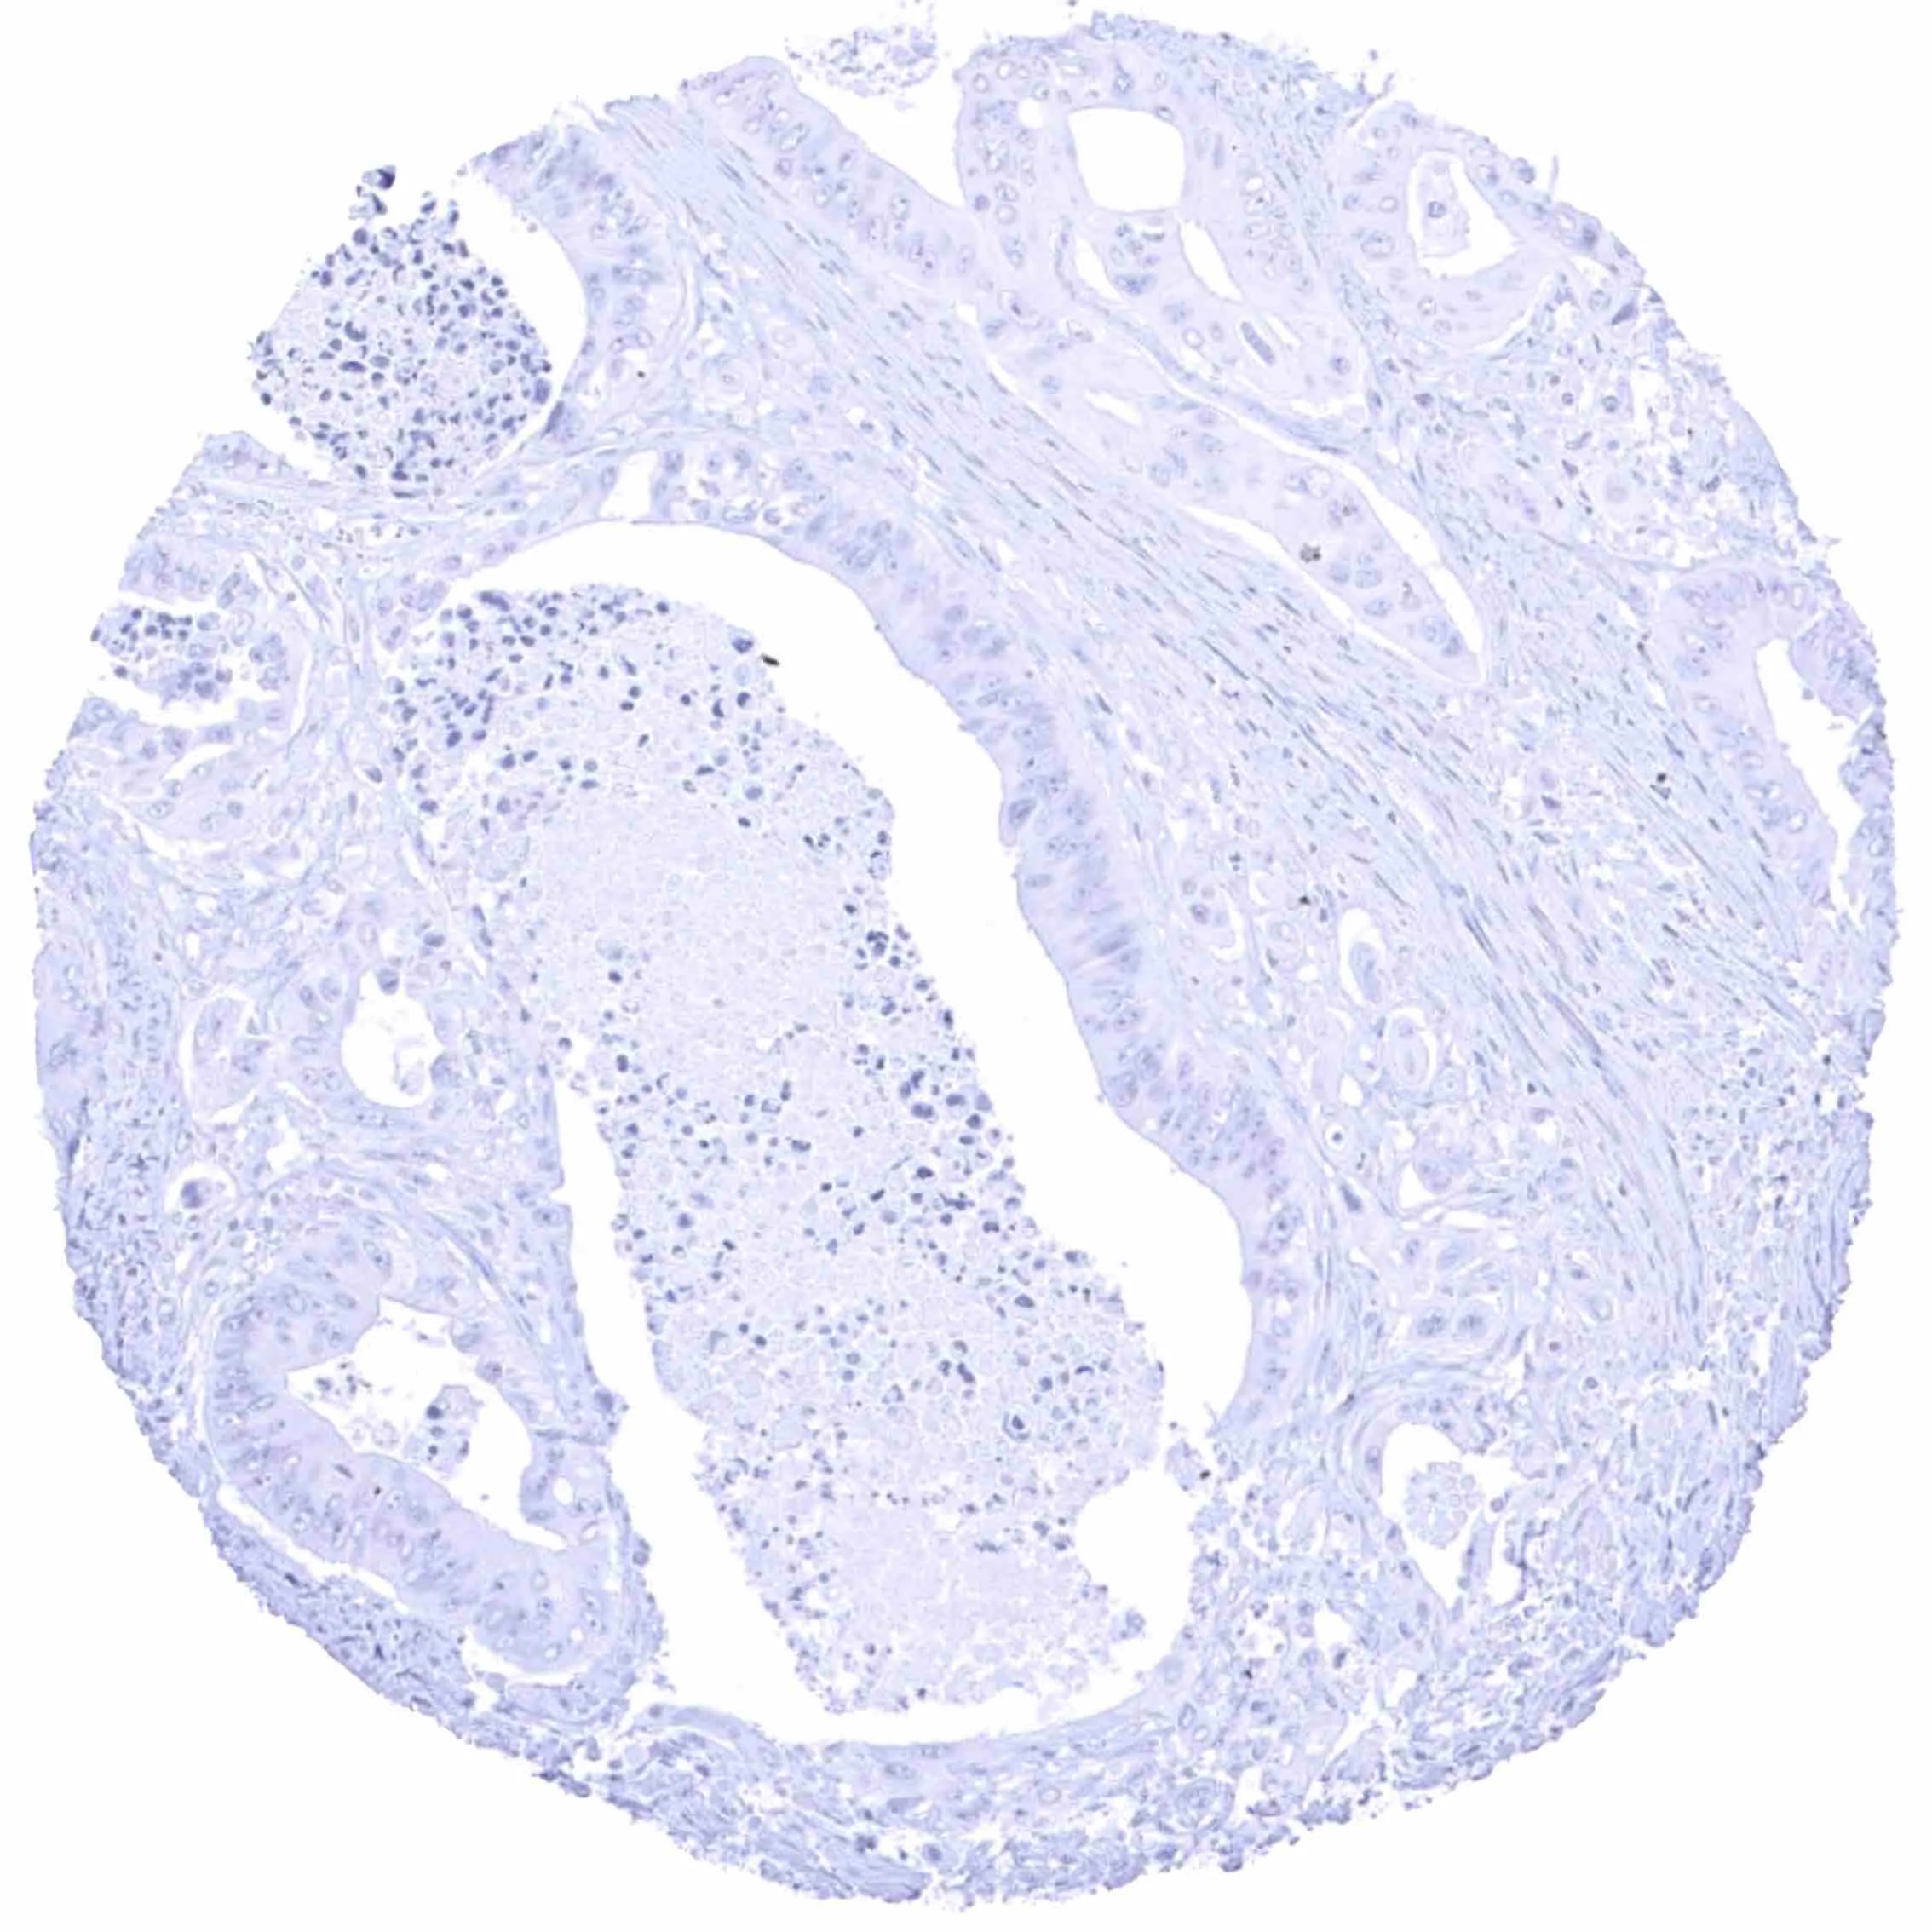

Urinary bladder – EGFRvIII negative muscle-invasive urothelial carcinoma.

Urinary bladder – EGFRvIII negative non-invasive papillary urothelial carcinoma (pTa).